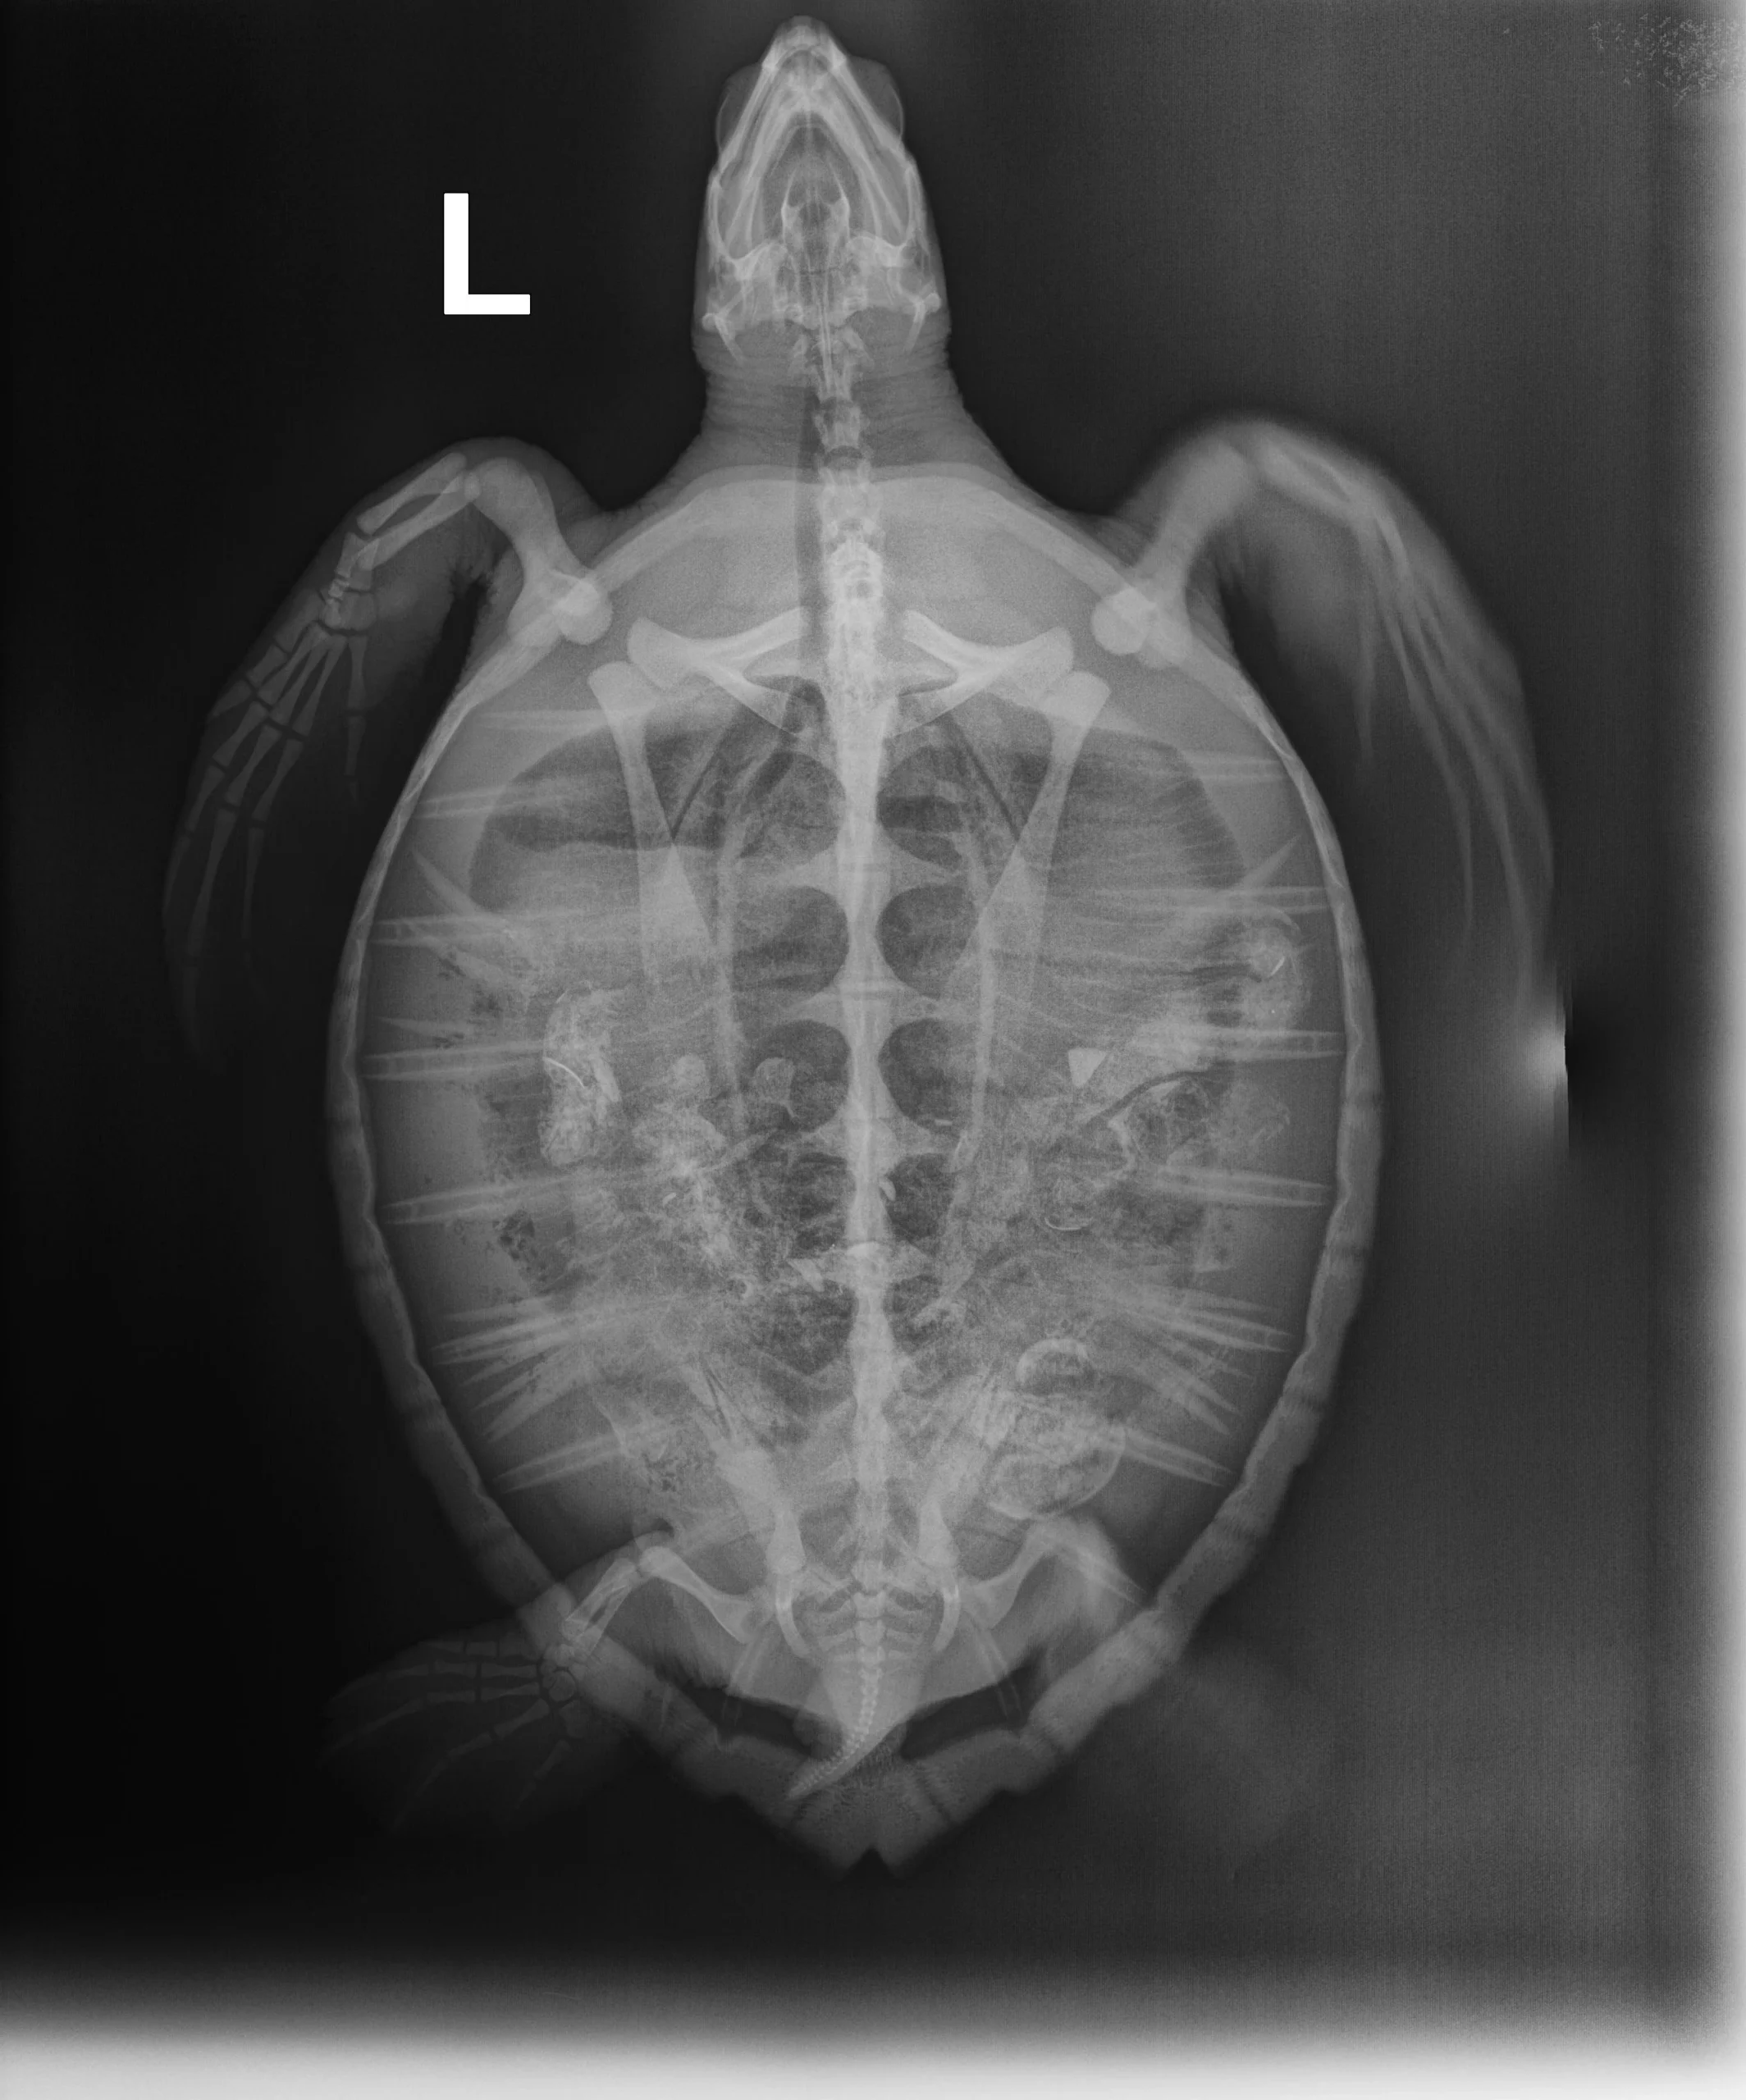

2.3 kg juvenile Atlantic Green sea turtle

Patient Injuries

Plastron: Minor abrasions

Head/Flippers/Soft Tissue: Abrasions on tips of both front flippers